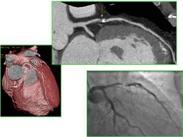

變異型心絞痛(variant angina pectoris)是以發(fā)作性急性心肌缺血為特征,但伴或不伴有典型心絞痛,伴有ST段抬高的臨床綜合征,是一種不穩(wěn)定型心絞痛。